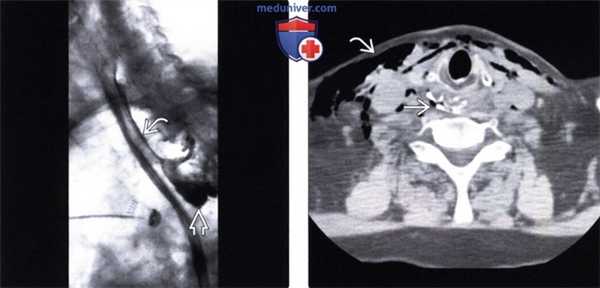

(Слева) На рентгенограмме пищевода, полученной у пациента с жалобами на боль в шее и грудной клетке, возникшей после введения зонда для энтерального питания, визуализируется газ и водорастворимый контраст в средостении позади пищевода. Выход контрастного вещества и газа за пределы просвета пищевода произошел в результате повреждения дивертикула Ценкера зондом. «Полоска» контрастного вещества распространяется параллельно задней стенке пищевода в проксимальных отделах.

(Справа) На аксиальной нативной КТ у этого же пациента определяется подкожная эмфизема, а также включения газа и контрастного вещества в мягких тканях превертебральной области.

(Слева) На рентгенограмме пищевода у мужчины 58 лет с жалобами на боль в груди после эндоскопического удаления куска пищи, вызвавшего обструкцию пищевода, определяется перфорация в дистальных отделах с утечкой контрастного вещества и газа в верхние отделы живота и в средостение, с наличием свободного газа под диафрагмой.

(Справа) На аксиальной нативной КТ у этого же пациента определяется свободный газ в полости брюшины, а также включения газа вдоль стенки пищевода и проксимальных отделов желудка. Лучевые данные идентичны таковым при синдроме Бурхаве.